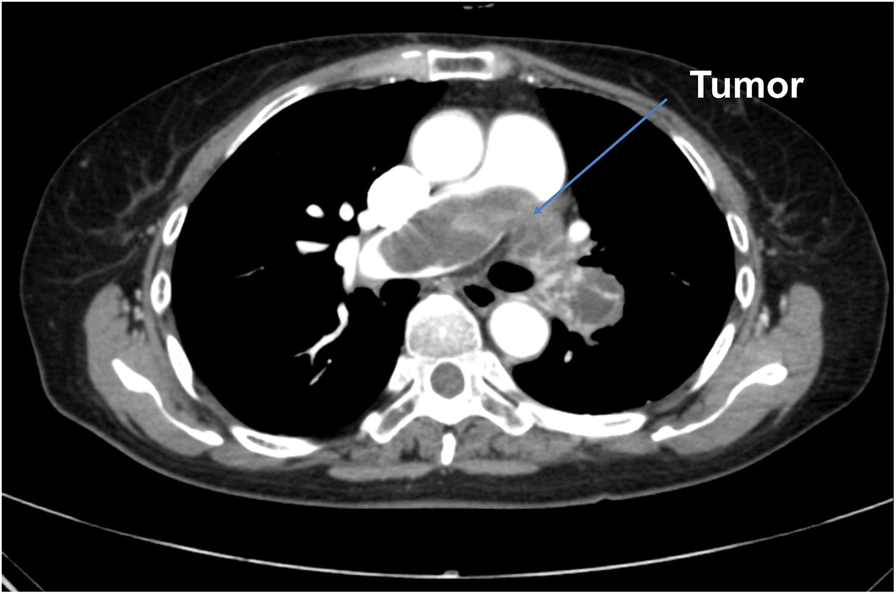

Occlusion of the pulmonary artery by a primary pulmonary artery